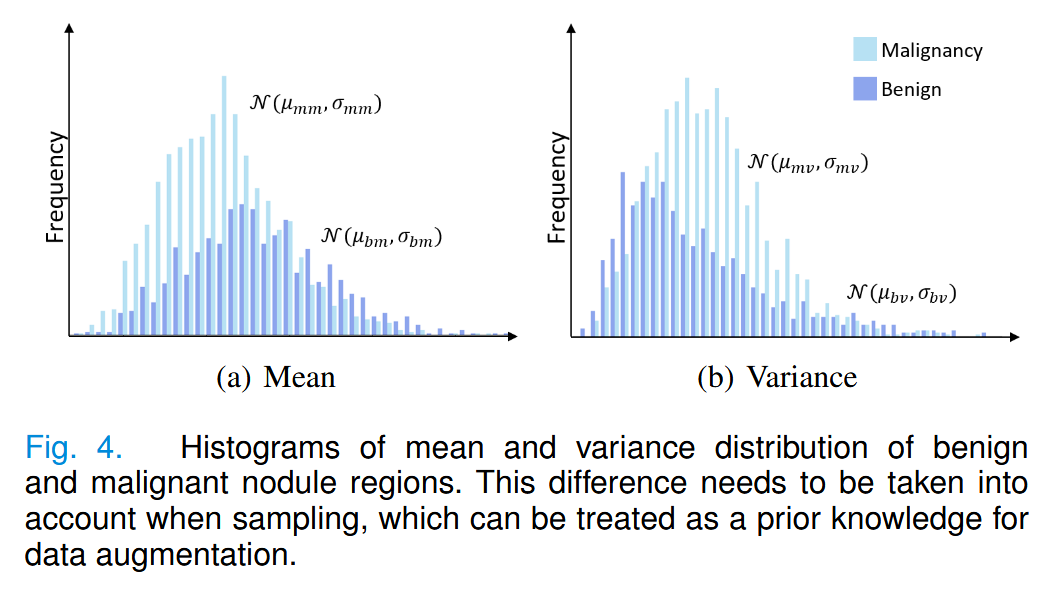

我们首先对良性和恶性结节的均值和方差进行了分布统计,发现存在一定差异,如图4所示。

因此,在数据生成的采样阶段,通过改变采样的条件分布来实现新样本的多样性。但同时也需要遵循数据的先验分布,以确保特征分布的合理性,如公式 15-18 所示,其中

\sigma(·)

σ(⋅) 如图4所示。